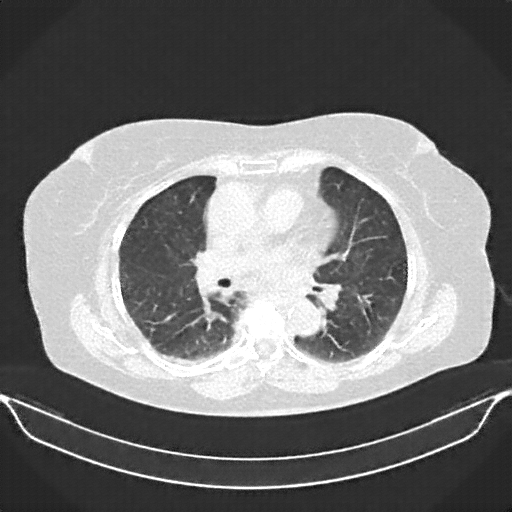

Original NATIVE CT scan (input)

Full window (WL 1023.5, WW 4095 β†’ Low βˆ’1024, High +3071)

Actual HU range: [-1024.0, 2210.0]